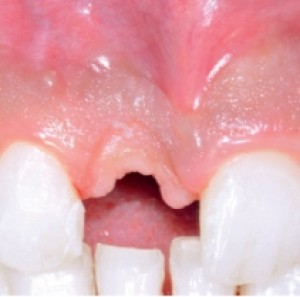

Obiettivi. Lo scopo di questo articolo è descrivere una serie di tecniche utili a migliorare l'estetica delle riabilitazioni implantari nel mascellare anteriore.Materiali e metodi. Si descrive...